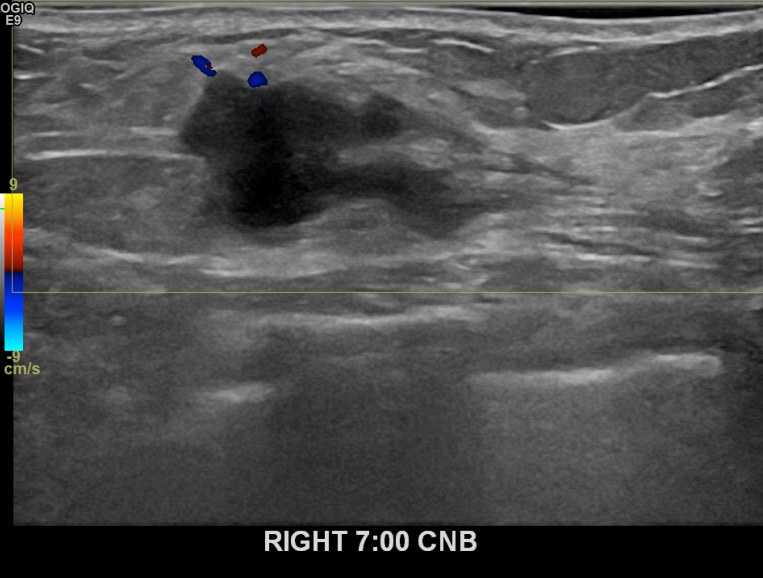

상기환자 건진상 이상소견으로 조직검사권유받고 내원하신 50대 여성분으로 우측유방멍울  조직검사시행후 유방암 진단되었습니다.